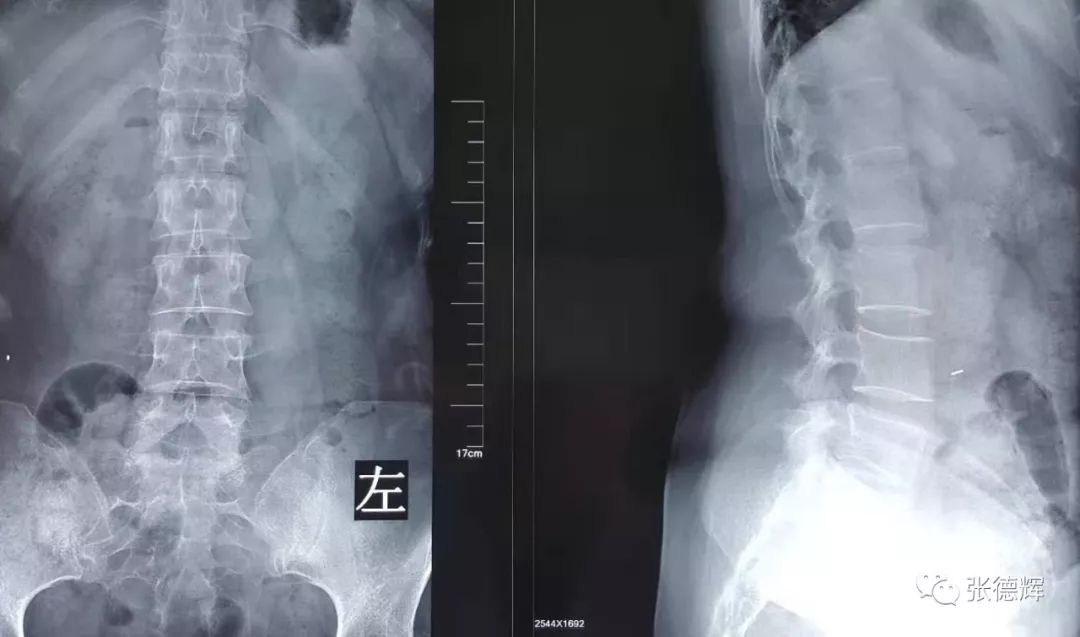

患者术前的各项影像检查

腰椎正侧位X光片及动力位片未见明显骨质结构异常及腰椎失稳